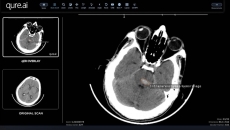

They will deploy AI to help reduce delays and gaps in stroke care management.